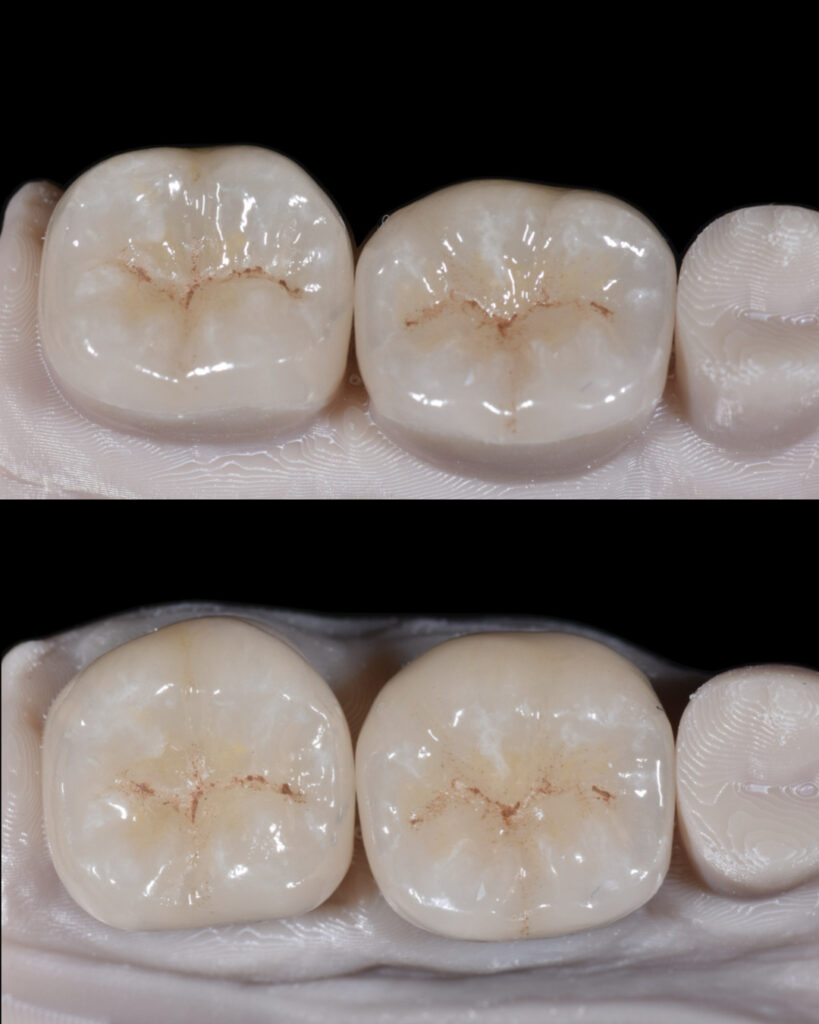

Tooth 3.6 was severely compromised and was managed with endodontic treatment, deep margin elevation, and an indirect adhesive restoration with full cuspal coverage using a lithium disilicate overlay.

Tooth 3.7 presented a large MOD carious lesion, with both distal cusps and the mesiolingual cusp structurally compromised.